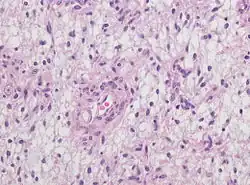

Neuropathology

Neuropathology is a specialty within the study of pathology focused on the disease of the brain, spinal cord, and neural tissue.[32] This includes the central nervous system and the peripheral nervous system. Tissue analysis comes from either surgical biopsies or post mortem autopsies. Common tissue samples include muscle fibers and nervous tissue.[33] Common applications of neuropathology include studying samples of tissue in patients who have Parkinson's disease, Alzheimer's disease, dementia, Huntington's disease, amyotrophic lateral sclerosis, mitochondria disease, and any disorder that has neural deterioration in the brain or spinal cord.[34][35]